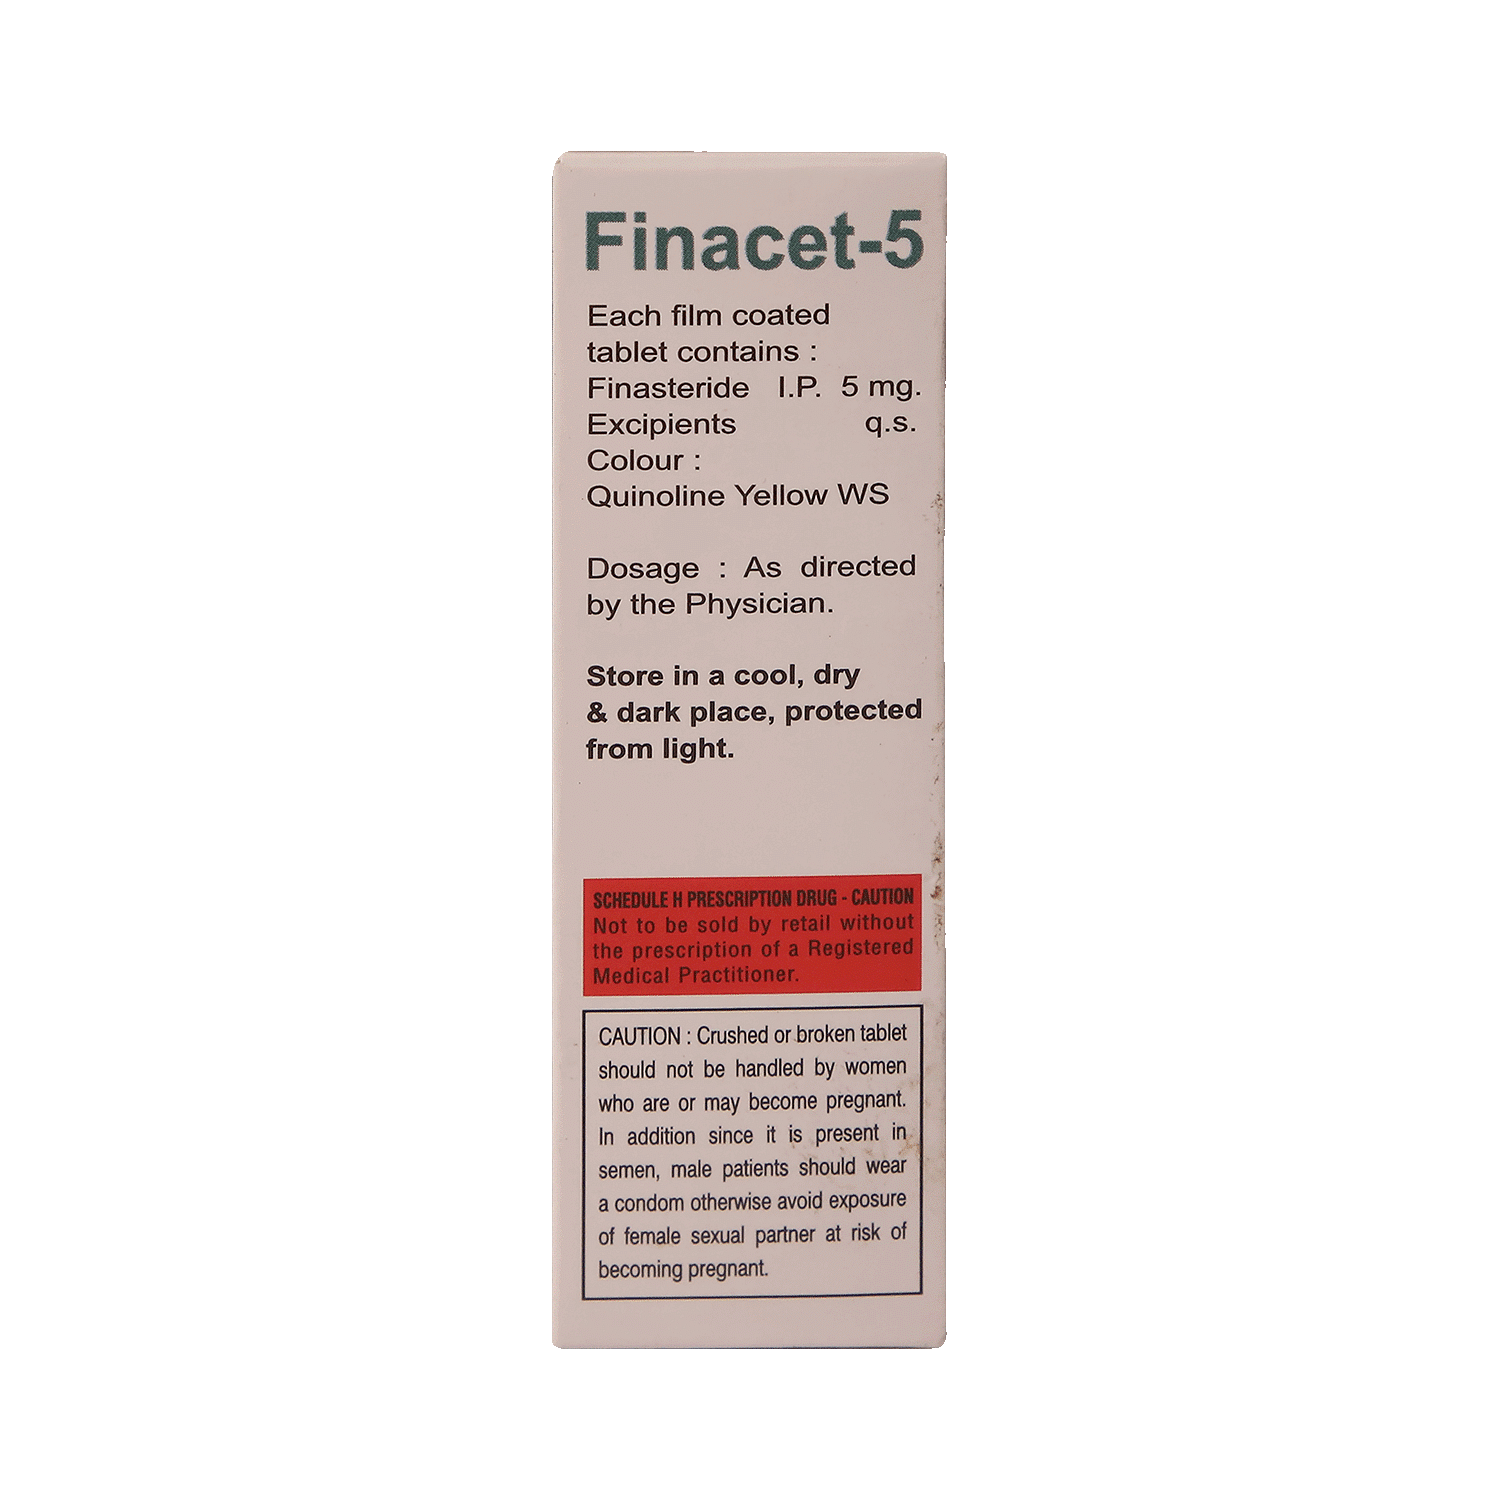

Finacet 5mg Tablet

Salt Composition

Finasteride (5mg)

Directions for Use

Take this medicine in the dose and duration as advised by your doctor. Swallow it as a whole. Do not chew, crush or break it. Finacet 5mg Tablet may be taken with or without food but it is better to take it at a fixed time.

Safety Information

Pregnancy Warning

Finacet 5mg Tablet is highly unsafe to use during pregnancy. Seek your doctor's advice as studies on pregnant women and animals have shown significant harmful effects to the developing baby.